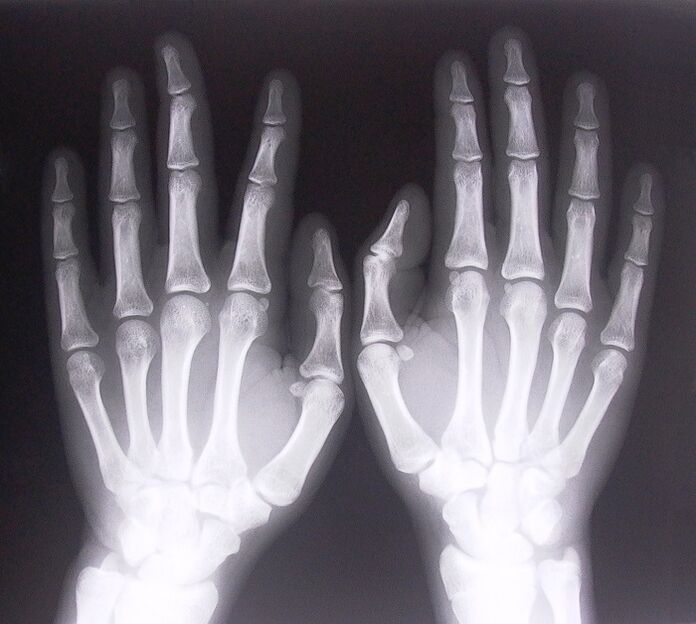

- Ligamentitis stenosing. Untuk menentukan punca penyakit, x-ray diperlukan. Gejala adalah tipikal: pergerakan tangan yang menyakitkan, gelung tapak tangan yang digenggam. Di samping itu, bunyi klik biasanya boleh didengar apabila memanjangkan.

- Ambil x-ray.